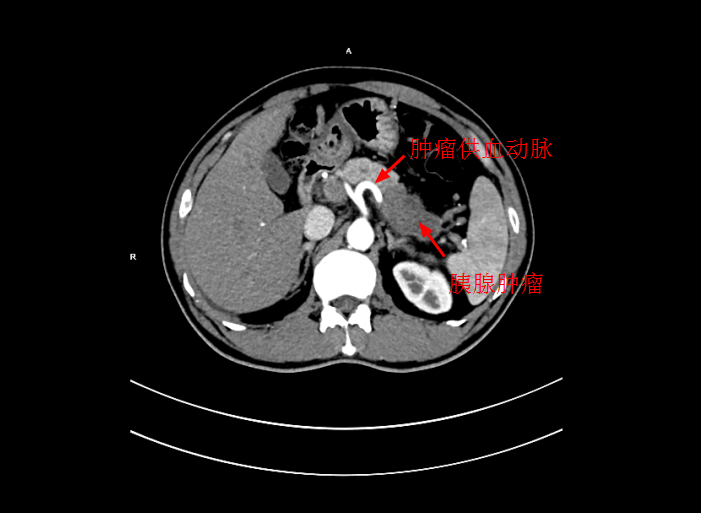

患者陳某,男,49歲,2個月前出現中上腹隐痛不适,伴有腰背部疼痛,在當地醫院就診,考慮爲胃窦炎、胃窦黃斑瘤,治療後症狀未見好轉,遂來我院就診。經過檢查後,确診爲局部晚期胰腺癌,大小爲5*3cm,癌細胞已侵犯胃窦。考慮到傳統化療方式,藥物經身體多重代謝後,到達胰腺的濃度低,達不到很好殺滅腫瘤組織的效果,且對正常組織具有一定的毒副作用。爲此李旭丹主任決定給予采用DSA下介入灌注化療,得到患者及其家屬的支持。

4月30日下午,李旭丹主任與胡志華主任上台實施介入化療術,在DSA造影下,清晰可見胰腺腫瘤的供血動脈,專家們将微導管經股動脈穿刺送達瘤體的供血動脈,成功将化療藥物灌注至瘤體,順利完成手術。術後,患者症狀明顯好轉,并于5月4日順利出院。